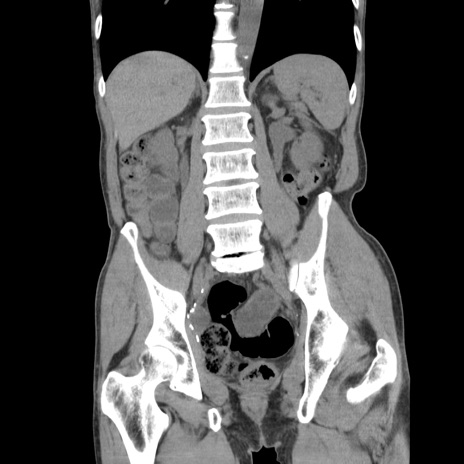

症例11(冠状断像)

【症例】 60歳代男性

【主訴】 下腹部痛

【現病歴】 本日夜中より下腹部痛の症状認め、受診。

【既往歴】 膀胱癌(膀胱全摘+尿管皮膚瘻術) 、胃癌術後

【身体所見】 BT 35.3℃、PR 58/min、BP 136/98mHg、腹部平坦、軟、腸蠕動音±、ストマ留置あり、左上腹部~正中部に圧痛あり、反跳痛なし。

【データ】WBC 5100、CRP0.01